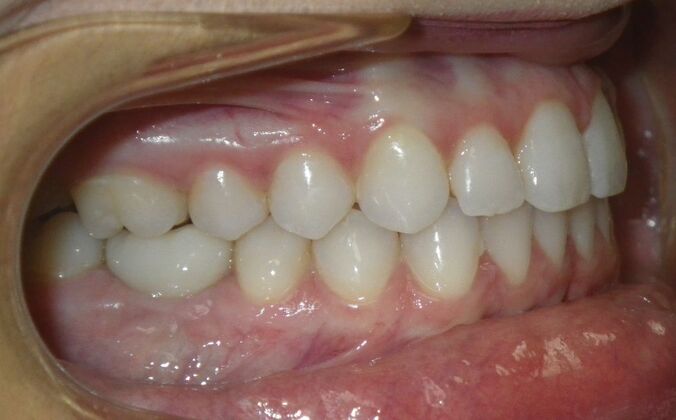

Invisalign: Case 17

This patient was an awesome dental assistant for our practice and we were all very sad when she had to move closer to her home. She was very interested in correcting some minor spacing and rotations in her upper and lower anterior teeth and to decrease her overbite as well.Treatment took about 12 months, but we were pleased with the results and fabricated clear invisalign vivera retainers. We are still hoping one day she will return to be with us again.